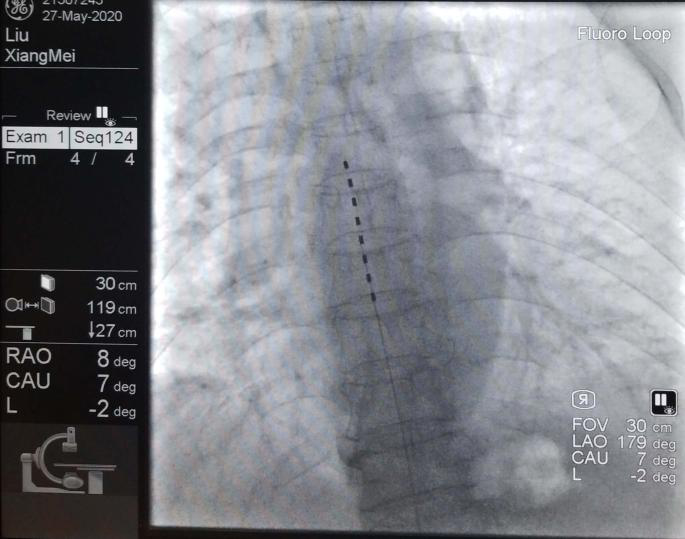

五、脊柱椎間孔鏡技術治療腰椎間盤突出癥。

六、關節鏡技術治療肩關節疼痛及肩袖損傷、膝關節滑膜炎、半月板損傷、游離體形成、腘窩囊腫等。

八、脊髓電刺激植入術治療帶狀皰疹后神經痛與頑固性疼痛。